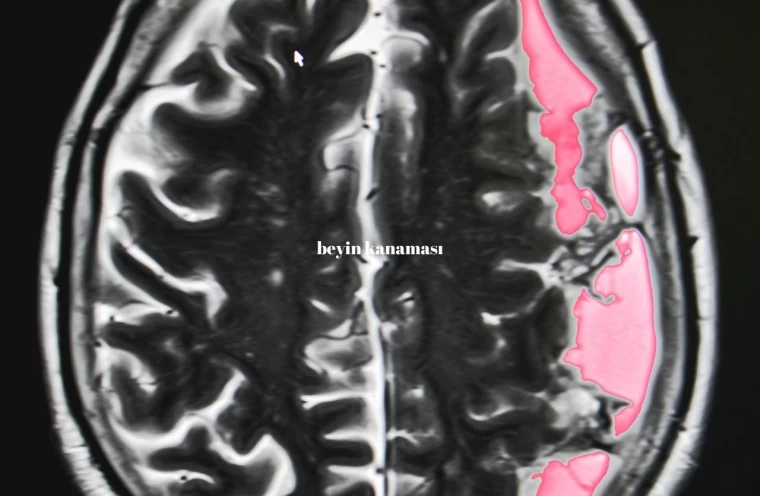

Beyin kanaması, aniden gelişen ciddi bir tıbbi durumdur ve beynin içerisindeki kan damarlarının patlaması sonucu meydana gelir. Bu durum, beynin normal fonksiyonlarını bozan bir basınca yol açar. Genellikle bir travma veya yüksek tansiyon gibi sebeplerden kaynaklanan beyin kanaması, anında müdahale gerektiren ve ölümcül sonuçlar doğurabilecek bir durumdur. Beyin kanamasının belirtilerini ve nasıl anlaşılabileceğini anlamak, erken müdahale şansını artırır. Bu yazıda, beyin kanaması belirtileri ve bu durumun risk faktörleri hakkında detaylı bilgi vereceğiz.

Beyin kanamasının ilk belirtileri, kanamanın yerine ve şiddetine bağlı olarak değişir. Ancak genel olarak, ani ve şiddetli baş ağrısı en yaygın belirtidir. Bunun yanında bulantı, kusma, görme bozuklukları, konuşma zorluğu, denge kaybı, yüz veya vücutta ani uyuşma ve bilinç bulanıklığı da görülebilir. Bu belirtiler, özellikle ani ve beklenmedik bir şekilde ortaya çıkıyorsa, derhal acil tıbbi yardım alınmalıdır. Zamanında müdahale, beyin kanamasının yol açabileceği kalıcı hasarların önlenmesinde kritik rol oynar.